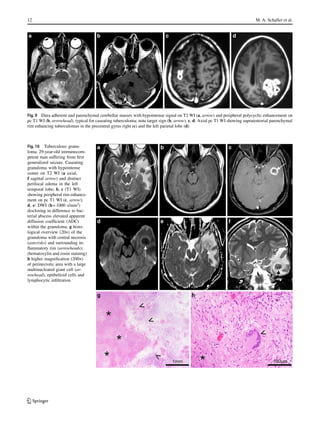

Fig. 9 Dura adherent and parenchymal cerebellar masses with hypointense signal on T2 WI (a, arrow) and peripheral polycyclic enhancement on

pc T1 WI (b, arrowhead), typical for caseating tuberculoma; note target sign (b, arrow). c, d: Axial pc T1 WI showing supratentorial parenchymal

rim enhancing tuberculomas in the precentral gyrus right (c) and the left parietal lobe (d)

Fig. 10 Tuberculous granu-

loma. 29-year-old immunocom-

petent man suffering from first

generalized seizure. Caseating

granuloma with hypointense

center on T2 WI (a axial,

f sagittal arrow) and distinct

perifocal edema in the left

temporal lobe; b, c (T1 WI)

showing peripheral rim enhance-

ment on pc T1 WI (c, arrow);

d, e: DWI (b= 1000 s/mm2

)

disclosing in difference to bac-

terial abscess elevated apparent

diffusion coefficient (ADC)

within the granuloma. g histo-

logical overview (20ร—) of the

granuloma with central necrosis

(asterisks) and surrounding in-

flammatory rim (arrowheads);

(hematoxylin and eosin staining)

h higher magnification (200ร—)

of perinecrotic area with a large

multinucleated giant cell (ar-

rowhead), epithelioid cells and

lymphocytic infiltration